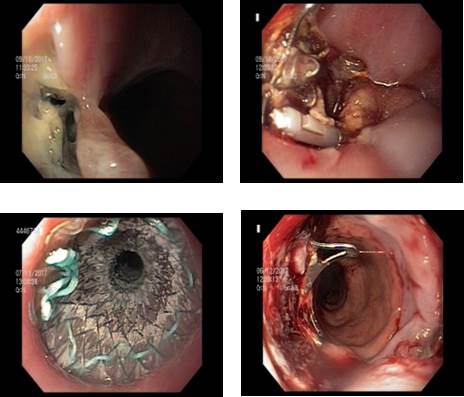

Figura 1. A) Orificio fistuloso subcardial. B) OVESCO y clips colocados para ocluir el orificio fistuloso. C) Colocación del stent. D) Imagen post retirada del stent a las 8 semanas donde ya no se observa el orificio fistuloso.

Se presenta el caso de una mujer de 35 años, raza blanca, obesa mórbida (IMC 44) sin otras comorbilidades a destacar, a la que se le realiza una GVL. Comienza al cuarto día del procedimiento con dolor abdominal difuso, fiebre de 38.5 °C, sin elementos de irritaciónn peritoneal. De la paraclínica sanguínea se destaca una leucocitosis de 14.000 células/mm³ y proteína C reactiva de 45 mg/L. En la tomografía de abdomen con contraste vía oral presenta burbujas de gas adyacentes a la línea de grapado. Con el planteo de falla de sutura se realiza laparoscopia exploradora para toilette peritoneal y colocación de drenaje, no se logra ver la dehiscencia en el intraoperatorio.

Luego de la

cirugía no reitera fiebre, presenta buen estado general, pero se constata

persistencia de gasto por drenaje constituyendo una fístula gástrica. Se

realiza video gastroscopia (VGC) donde se visualiza orificio fistuloso

inmediatamente por debajo de la unión gastro esofágica, sobre la línea de

sutura. Se coloca clip Ovesco® (12mm, tipo gc, marca Ovesco, Tübingen,

Alemaña) a nivel del orificio fistuloso con posterior

colocación de 2 clips y sonda nasoyeyunal de alimentación con el objetivo de

asegurar el cierre de la misma y asegurar una correcta nutrición

respectivamente. Se realiza estudio contrastado de esófago gastro duodeno de

control a las 3 semanas, observando la persistencia de fuga de contraste a

nivel del orificio fistuloso. Se decide la colocación de stent metálico

autoexpandible parcialmente recubierto ((23/18 mm de diámetro, Boston

Scientific Corporation, Natick, MA, USA) para ocluir el orificio fistuloso.

Presenta buena evolución a las 48 horas, con disminución franca del gasto por

el drenaje, que posteriormente se agota (figura.1).

Se realizó la extracción del stent a las 8 semanas

tras su colocación, sin incidentes. La cicatrización de la fuga se confirmó

mediante endoscopia e inyección de contraste.